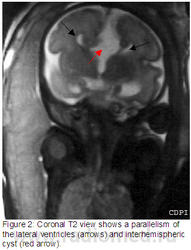

2. На коронарной Т2 параллельность боковых желудочков (стрелки) и межполушарная киста (красная стрелка).